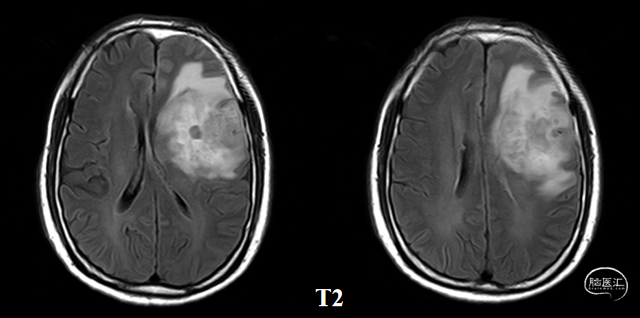

术后48小时MR,可见左额不规则混杂信号影,周围水肿:图示。

术后48小时MR,增强后边缘不规则线样强化,靠近放射冠及侧脑室壁可疑少许残存:图示。

入院前头MRI(2020-3):左侧额岛叶肿块,信号不均匀,其内可见出血和坏死,占位效应明显,周围见水肿。考虑左额岛叶肿瘤(高级别脑胶质瘤可能性大)。于2020年4月行左额岛叶占位性病变切除术。术中见肿瘤组织位于左侧额中回及额下回后部,大小约4m×5cm×5cm,呈烂鱼肉样,色灰红,质软,部分坏死,血运中等,边界不清,侵犯左侧岛叶向下挤压颞叶。显微镜下沿肿瘤周边胶质增生带完整切除肿瘤。术后48小时内复查头MRI平扫、加强,影像显示术腔边缘不规则线样强化,靠近放射冠及侧脑室壁强化明显,可疑少许残存。